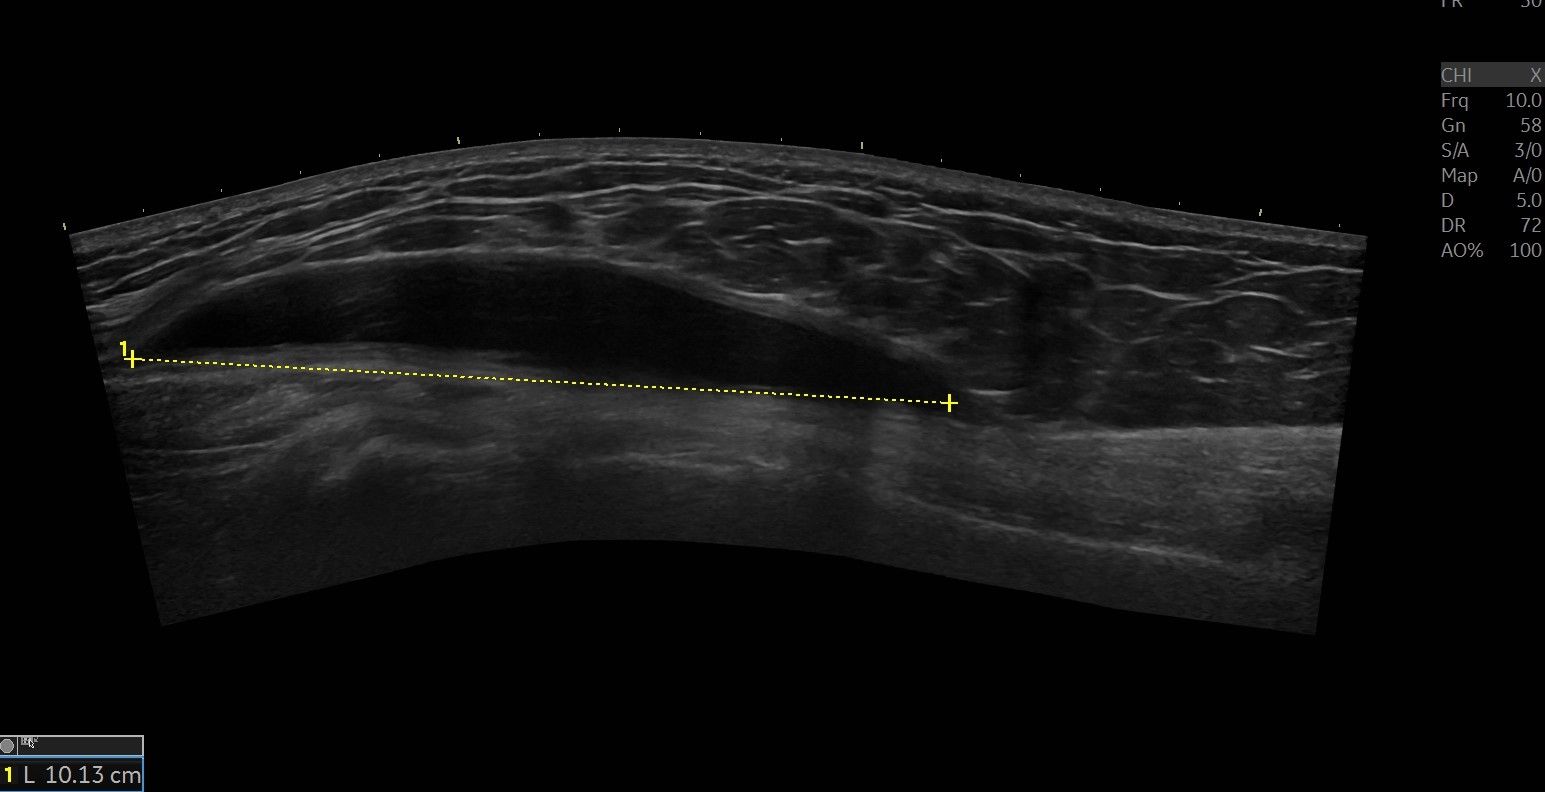

An ultrasound examination shows local bursitis over trochanter.

We aspirated the bursa with 30 ml of clear fluid and then injected cortisone.

Below you can see the ultrasound images before, during, and after the treatment.

Bursit longitudinell projektion